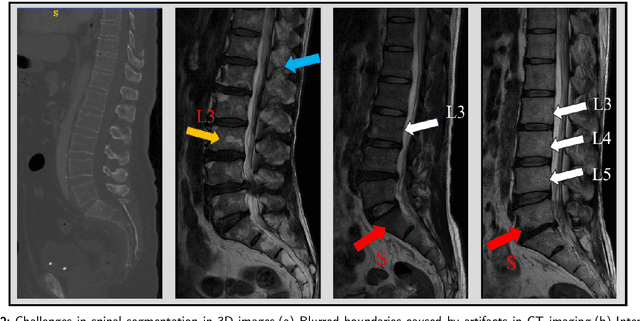

Abstract:Accurate segmentation of 3D clinical medical images is critical in the diagnosis and treatment of spinal diseases. However, the inherent complexity of spinal anatomy and uncertainty inherent in current imaging technologies, poses significant challenges for semantic segmentation of spinal images. Although convolutional neural networks (CNNs) and Transformer-based models have made some progress in spinal segmentation, their limitations in handling long-range dependencies hinder further improvements in segmentation accuracy.To address these challenges, we introduce a residual visual Mamba layer to effectively capture and model the deep semantic features and long-range spatial dependencies of 3D spinal data. To further enhance the structural semantic understanding of the vertebrae, we also propose a novel spinal shape prior module that captures specific anatomical information of the spine from medical images, significantly enhancing the model's ability to extract structural semantic information of the vertebrae. Comparative and ablation experiments on two datasets demonstrate that SpineMamba outperforms existing state-of-the-art models. On the CT dataset, the average Dice similarity coefficient for segmentation reaches as high as 94.40, while on the MR dataset, it reaches 86.95. Notably, compared to the renowned nnU-Net, SpineMamba achieves superior segmentation performance, exceeding it by up to 2 percentage points. This underscores its accuracy, robustness, and excellent generalization capabilities.